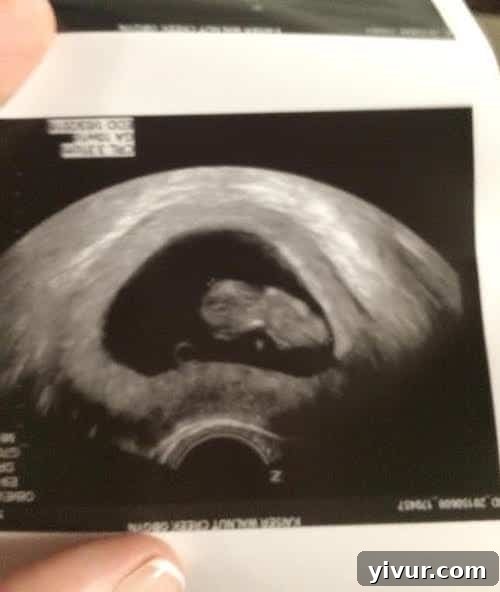

14 Week Ultrasound showing a healthy baby, a significant milestone in the pregnancy journey.

Last Wednesday, we attended our 13-week appointment, and the wonderful news is that our baby is healthy and strong! There was no risk for Down syndrome, and the baby was even measuring a full week larger than expected for a 13-week pregnancy. This delightful surprise shifted my due date from January 6th to December 29th, essentially moving me forward a whole week in my pregnancy! Shawn and I were overjoyed to confirm a healthy baby and celebrated with a special pizza date afterward. It was extra special because I was finally able to eat and truly enjoy the pizza, a significant improvement from previous weeks.